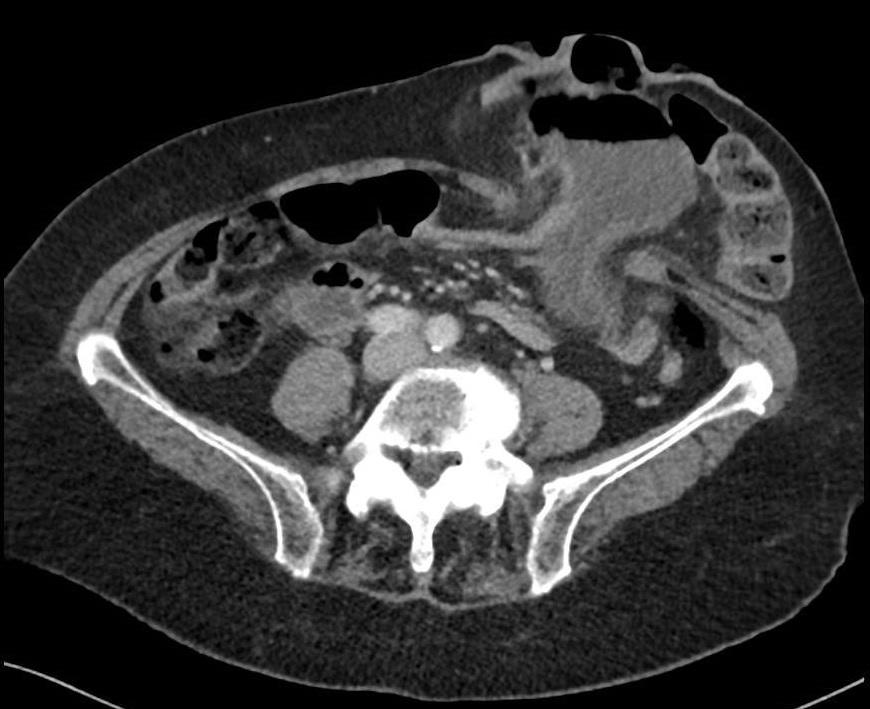

Een 88-jarige vrouw krijgt plotseling last van hevige misselijkheid en braken. Zij heeft sinds 6 jaar een eindstandig colostoma in de linker onderbuik na een curatieve resectie van een rectumcarcinoom. Het gebied rond het stoma is drukpijnlijk. Wegens een klinische verdenking op een hoge gastro-intestinale obstructie wordt er een CT-scan gemaakt.

Wat is uw diagnose?